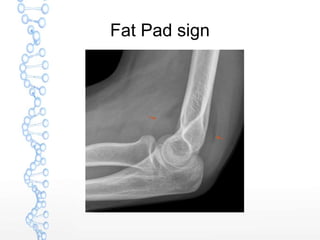

RADIOLOGY

 Standard Anteroposterior and Lateral

radiographs of the elbow

Fat Pad sign